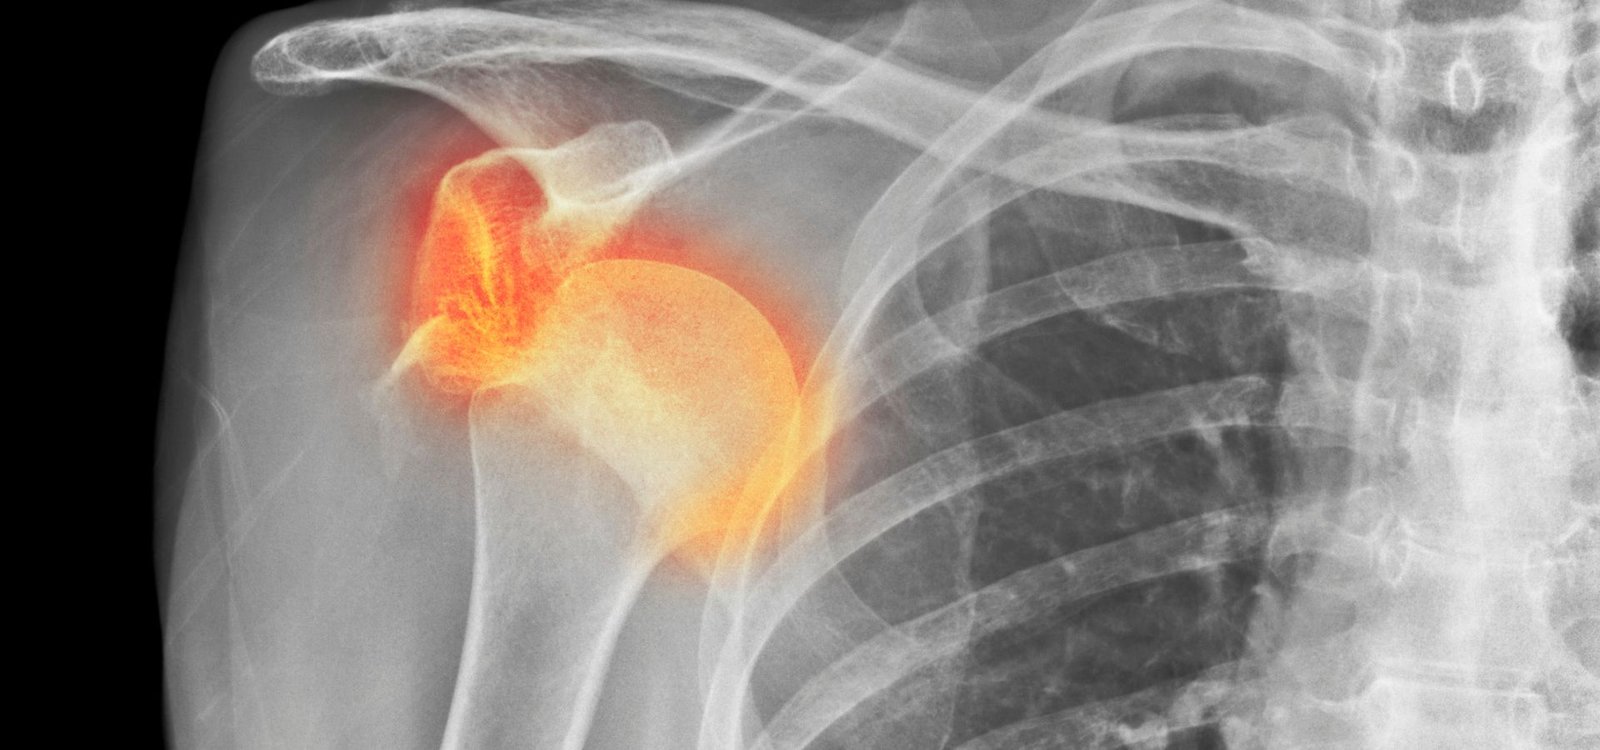

Shoulder dislocation occurs when the upper arm bone slips out of its socket. It often happens due to sports injuries, falls, or sudden impact.

During dislocation, the ball of the upper arm moves out of the shoulder socket. This can damage ligaments, cartilage, and surrounding tissues.